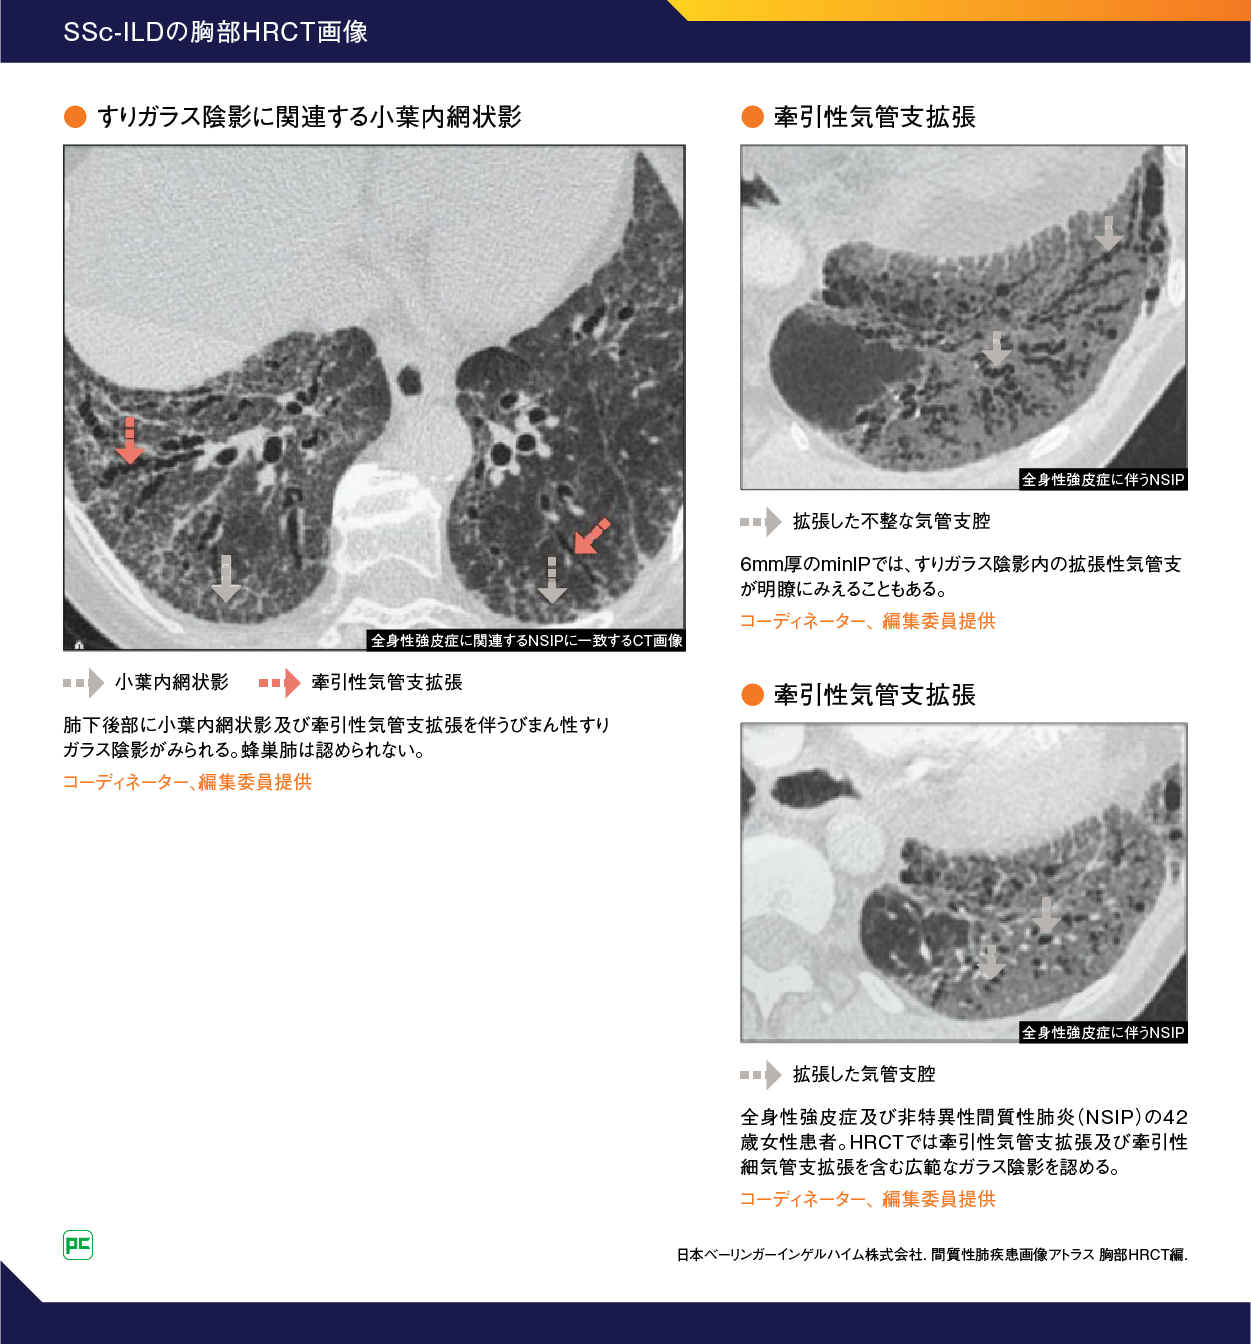

SSc-ILDのスクリーニング、診断、重症度評価において、胸部HRCT検査は従来の胸部CT検査や呼吸機能検査よりも感度が高いため、今回の改訂においてもILDのリスクが高いSSc患者での胸部HRCT検査によるスクリーニングが推奨されています1)。SSc-ILD患者の胸部HRCT所見を提示します(図4)9)。

図4

SSc-ILDの胸部HRCT所見は特発性非特異性間質性肺炎(iNSIP)と類似の非特異性間質性肺炎(NSIP)パターンを呈し、すりガラス影主体、すりガラス影と網状影の混在が主で、蜂巣肺形成はまれとされています10)。

また、SSc-ILD患者でみられるすりガラス影は経過のなかで牽引性気管支拡張へと変化することがあります10)。このように、すりガラス影が牽引性気管支拡張へと進行する理由として、すりガラス影が炎症だけでなく小葉内の線維化を反映していることが要因と推測されています 11)。

SScでみられるNSIPパターンの線維化は、びまん性といってもやや強弱があることが多く、炎症細胞浸潤に乏しい時相の均一な慢性線維化がやや小葉/細葉辺縁優位に分布し、細かな網目状に繋がるような像が1つの典型像となります1)。